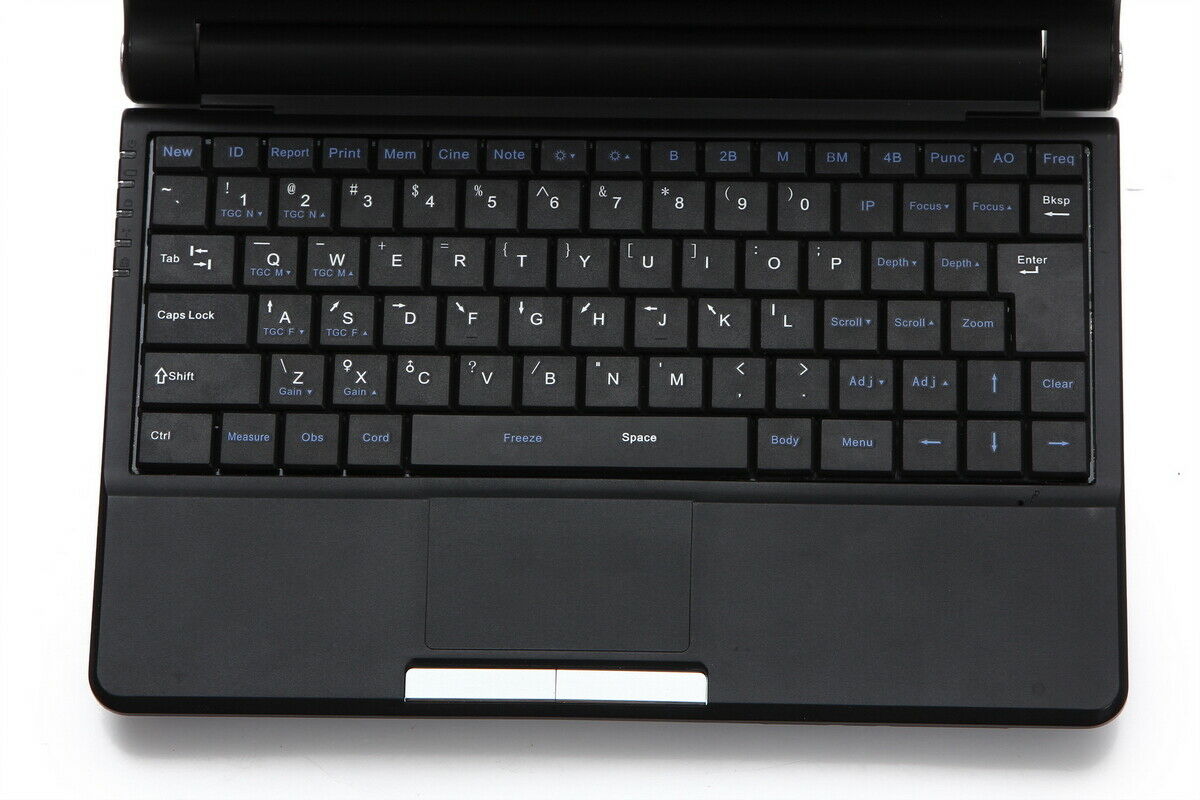

In terms of user interface, the TFT LCD Digital Laptop Linear Array Ultrasound Scanner comes with intuitive software that allows operators to navigate through different settings and functions effortlessly. This reduces the learning curve and means even new users can quickly become proficient in its use. The software is regularly updated, ensuring that you have access to the latest features and improvements.